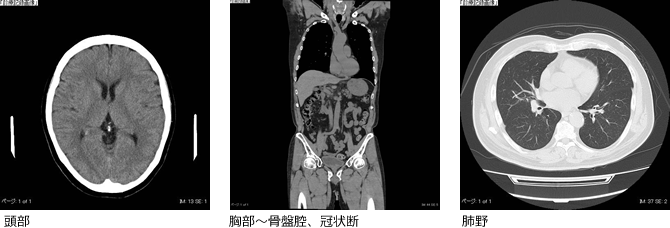

- CT検査

- 当院では、高性能の80列マルチスライスCTスキャナを設置しております。従来のものと比較し、より低被ばく・高画質な撮影が可能となりました。検査は患者さんが寝台に横になるだけで苦痛なく頭部や胸部、腹部の断層像(輪切り)を鮮明に撮ることができます。とても簡単で短時間ながら広範囲の撮影がおこなえ、頭部外傷・脳出血・脳梗塞等の頭部疾患から胸部疾患および腹部臓器(肝・胆・膵・腎・膀胱・その他)疾患にいたるまで、全身の診断が可能です。そして、架台開口径780mmの大型スキャンは今まで懸念されがちだった圧迫感も感じることなく、リラックスしながら安心して検査を受けることができます。

所要時間:約5~10分